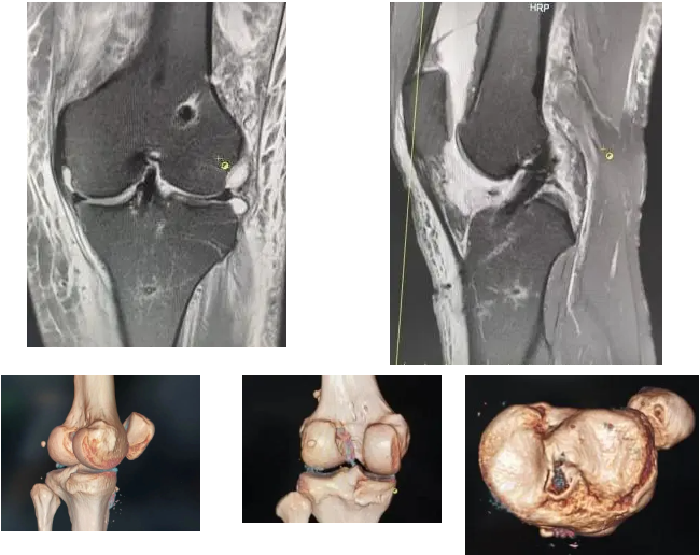

术前MRI提示:

左膝前交叉韧带损伤,左膝内外侧半月板损伤

术后第二天复查影像:

MRI、三维CT重建显示重建韧带位置及张力良好